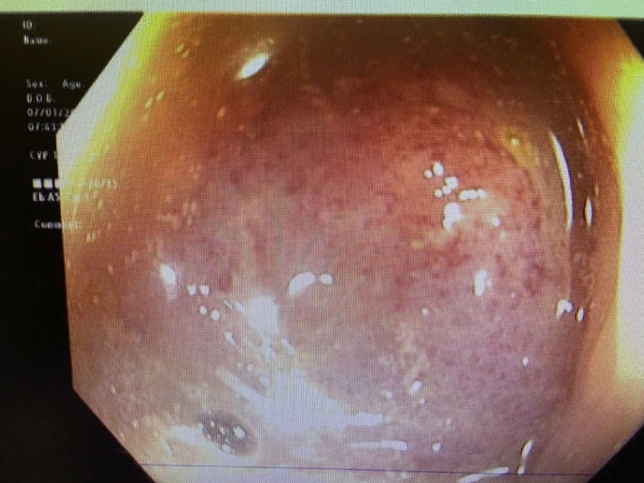

Methods: We present a 72-year-old male with prior radical cystectomy and neobladder creation complicated at the time by neobladder-cutaneous fistula and wound infection requiring revisional surgery and incisional hernia repair with mesh. He developed a large recurrent incisional hernia and underwent open hernia repair with bilateral anterior component separation, extensive lysis of adhesions, removal of prior mesh, and placement of a biologic mesh (Strattice™ RTM) in an underlay and onlay fashion. Intraoperatively, the defect measured 20 cm long by 14 cm wide. Postoperatively, he was treated for neobladder infection and CT cystogram found no extravasation from the neobladder. He presented to the emergency department 6 weeks after surgery with spontaneous partial midline wound dehiscence, with exposure of the onlay mesh and drainage of clear fluid, which was confirmed to be urine by fluid creatinine level. Repeat CT scan demonstrated a filling defect at the anterior wall of the neobladder with contrast leaking into a contained collection interposed between the anterior abdominal wall and the underlay mesh, extending superiorly between the small bowel loops and dehiscence of the midline abdominal wound. The patient was treated with a course of antibiotics and indwelling Foley catheter and bilateral nephrostomy tubes for urine diversion.

Results: Three months later, repeat CT cystogram demonstrated resolution of the leak and the nephrostomy tubes and Foley catheter were removed. The patient has continued daily wound care with significant reduction in size of the midline wound and increasing granulation tissue around the onlay mesh. He has not required further admissions to hospital and there has been no hernia recurrence so far.